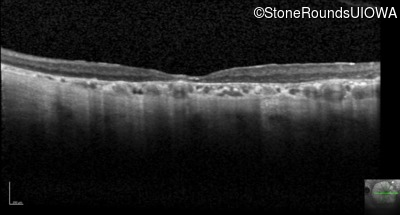

Optical Coherence Tomography - Right - 20/160 +2 sc

Exemplar / OCT Stack

OCT Stack